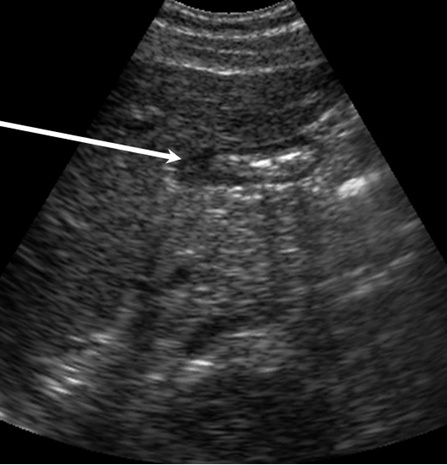

Bild 2: Gallenblase, Luftblasen im Duodenum

Pfeil: Luftblasen im Duodenum